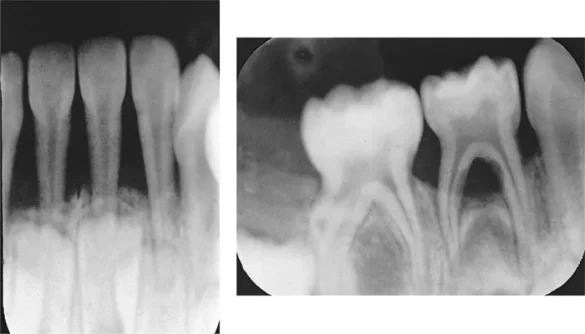

Periodontitis is a more advanced stage of gum disease. In this stage, the inflammation extends deeper into the supporting tissues and bone, potentially leading to tooth loss if not properly managed. There are different types of periodontitis, ranging from moderate to severe, depending on the extent of the damage.

Loss of Bone Support: As the disease advances, the infection begins to affect the bone and tissue that support the teeth.

The bone begins to break down, and the teeth lose their anchor. This process is called bone resorption.

Mobility of Teeth: As the bone loss becomes more severe, the teeth can become loose and unstable. This is often a sign that the disease has reached a critical point, and tooth loss may be imminent.